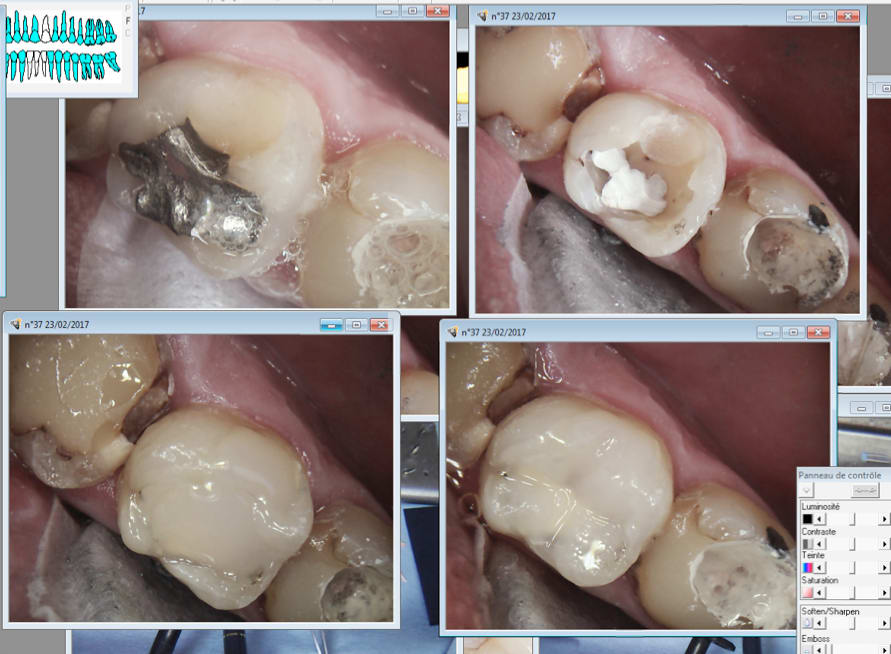

Ici bulk fill 5 mn. Le compo du pauvre. Future endo ic coiffe.

Capture d écran 2017 02 23 10.20 - Eugenol